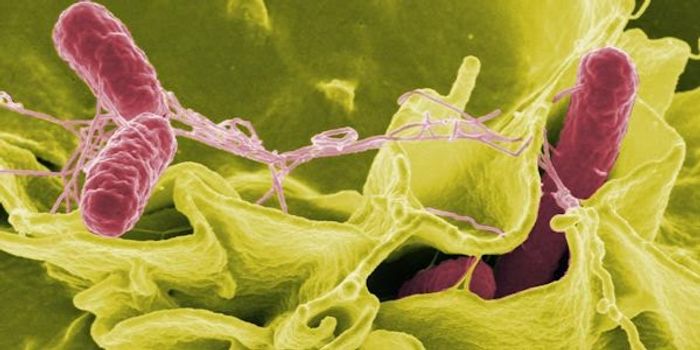

AUG 07, 2017Clinical & Molecular DXInvestigations into why people across 16 states have gotten sick with salmonella poisoning yielded the culprit: contamin ...

JAN 11, 2017CancerSalmonella, the bacteria that is bane of all restaurants and grocery stores, has now been transformed into “tumor- ...